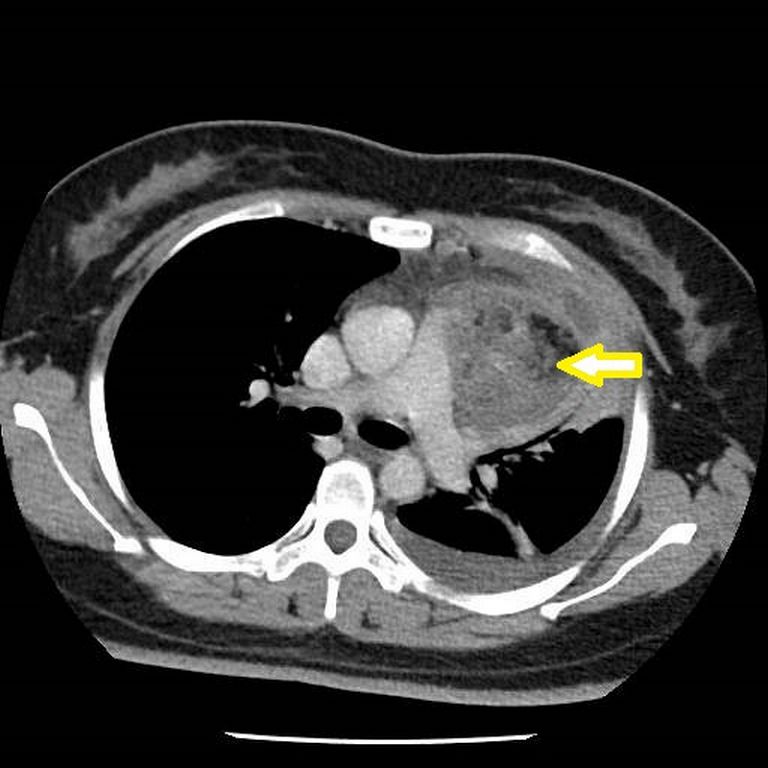

28歲的張小姐前陣子因為左手痛,陸續到診所看中醫與復健科,但是三個月過去都沒有顯著改善,狀況還越來越嚴重,連舉手都有困難。疼痛部位蔓延到肩背,一日更痛到無法離開床上、全身發冷,到醫學中心檢查發現她的胸腔有一顆相當巨大的腫瘤。張小姐因畏懼手術,在處理急性症狀後先行返家,但數天後再次因胸痛、背痛、咳嗽到無法平躺來到台北慈濟醫院。檢查發現,位於前縱膈腔的腫瘤有7公分大,已經壓迫神經,胸腔外科洪嘉聰醫師以開胸手術將腫瘤取出,經過化驗,確定是有頭髮、牙齒、肌肉、氣管黏膜和腦組織的成熟畸胎瘤。而張小姐因腫瘤造成的肺積水、咳嗽、手痛都在術後逐漸康復,並透過持續的肺部復健找回健康。

洪嘉聰醫師說明,畸胎瘤是出生就存在的於人體的腫瘤,但是否有症狀會因腫瘤大小而異,以張小姐為例,她的畸胎瘤在胸腔逐漸增大,壓迫肺臟且侵犯肋膜造成疼痛,走路需要依賴氧氣,嚴重影響生活。而且這個畸胎瘤的位置臨近主動脈、肺動脈及無名靜脈,若以胸腔鏡微創手術切除有大出血風險,因此醫療團隊選擇正中胸骨切開術,將胸骨鋸開後,將腫瘤與周邊的血管、組織的沾黏撥離,最後將腫瘤完整取下。洪嘉聰醫師提到,畸胎瘤最適切的切除方式是在不弄破的情況下完整切除,以免腫瘤組織或細胞掉落體內未清除乾淨,造成感染或復發。